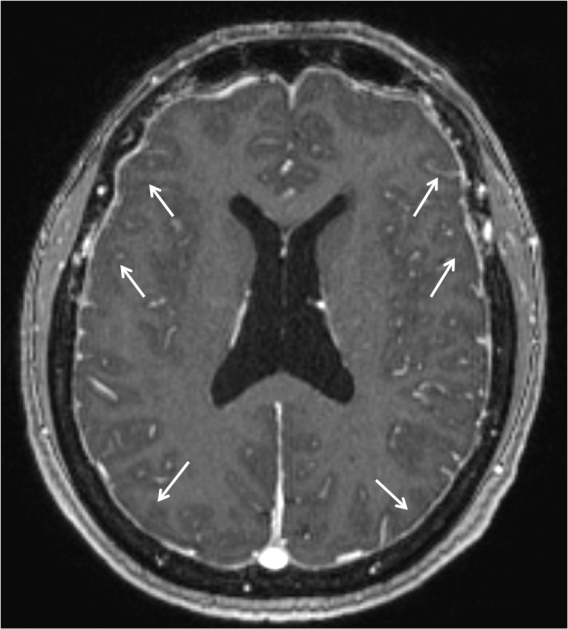

En la Imagen 6 y 7, se pude observar la captación dural de contraste que se debe a la mayor concentración de contraste (gadolinio) en la vasculatura y fluido intersticial de la duramadre. Esta hipercaptación afecta a la duramadre (paquimeninge) y no a las leptomeninges (aracnoides y piamadre) por lo que no afecta a la profundidad de los surcos corticales ni alrededor del tronco cerebral, es continuo no nodular y afecta a los compartimentos supra e infratentorial. En la Imagen 1 se observa también el engrosamiento dural sin contraste en fosa posterior y primeros segmentos cervicales.